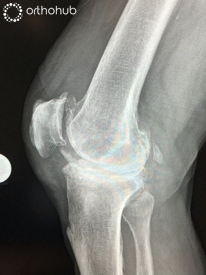

AP and Lateral radiographs

77 year old lady in severe pain in her knee. She had a previous open lateral meniscectomy at age 20, and a further open procedure for 'problems with her knee cap' 30 years ago.

On examination she has a clinical valgus deformity, and an elevated BMI.